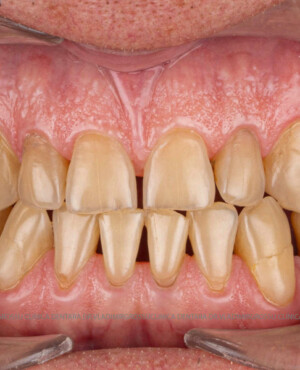

- Perioada de osteointegrare (3–6 luni)

- Amprentarea digitală sau clasică a zonei

- Realizarea lucrării protetice (coroană, punte sau proteză)